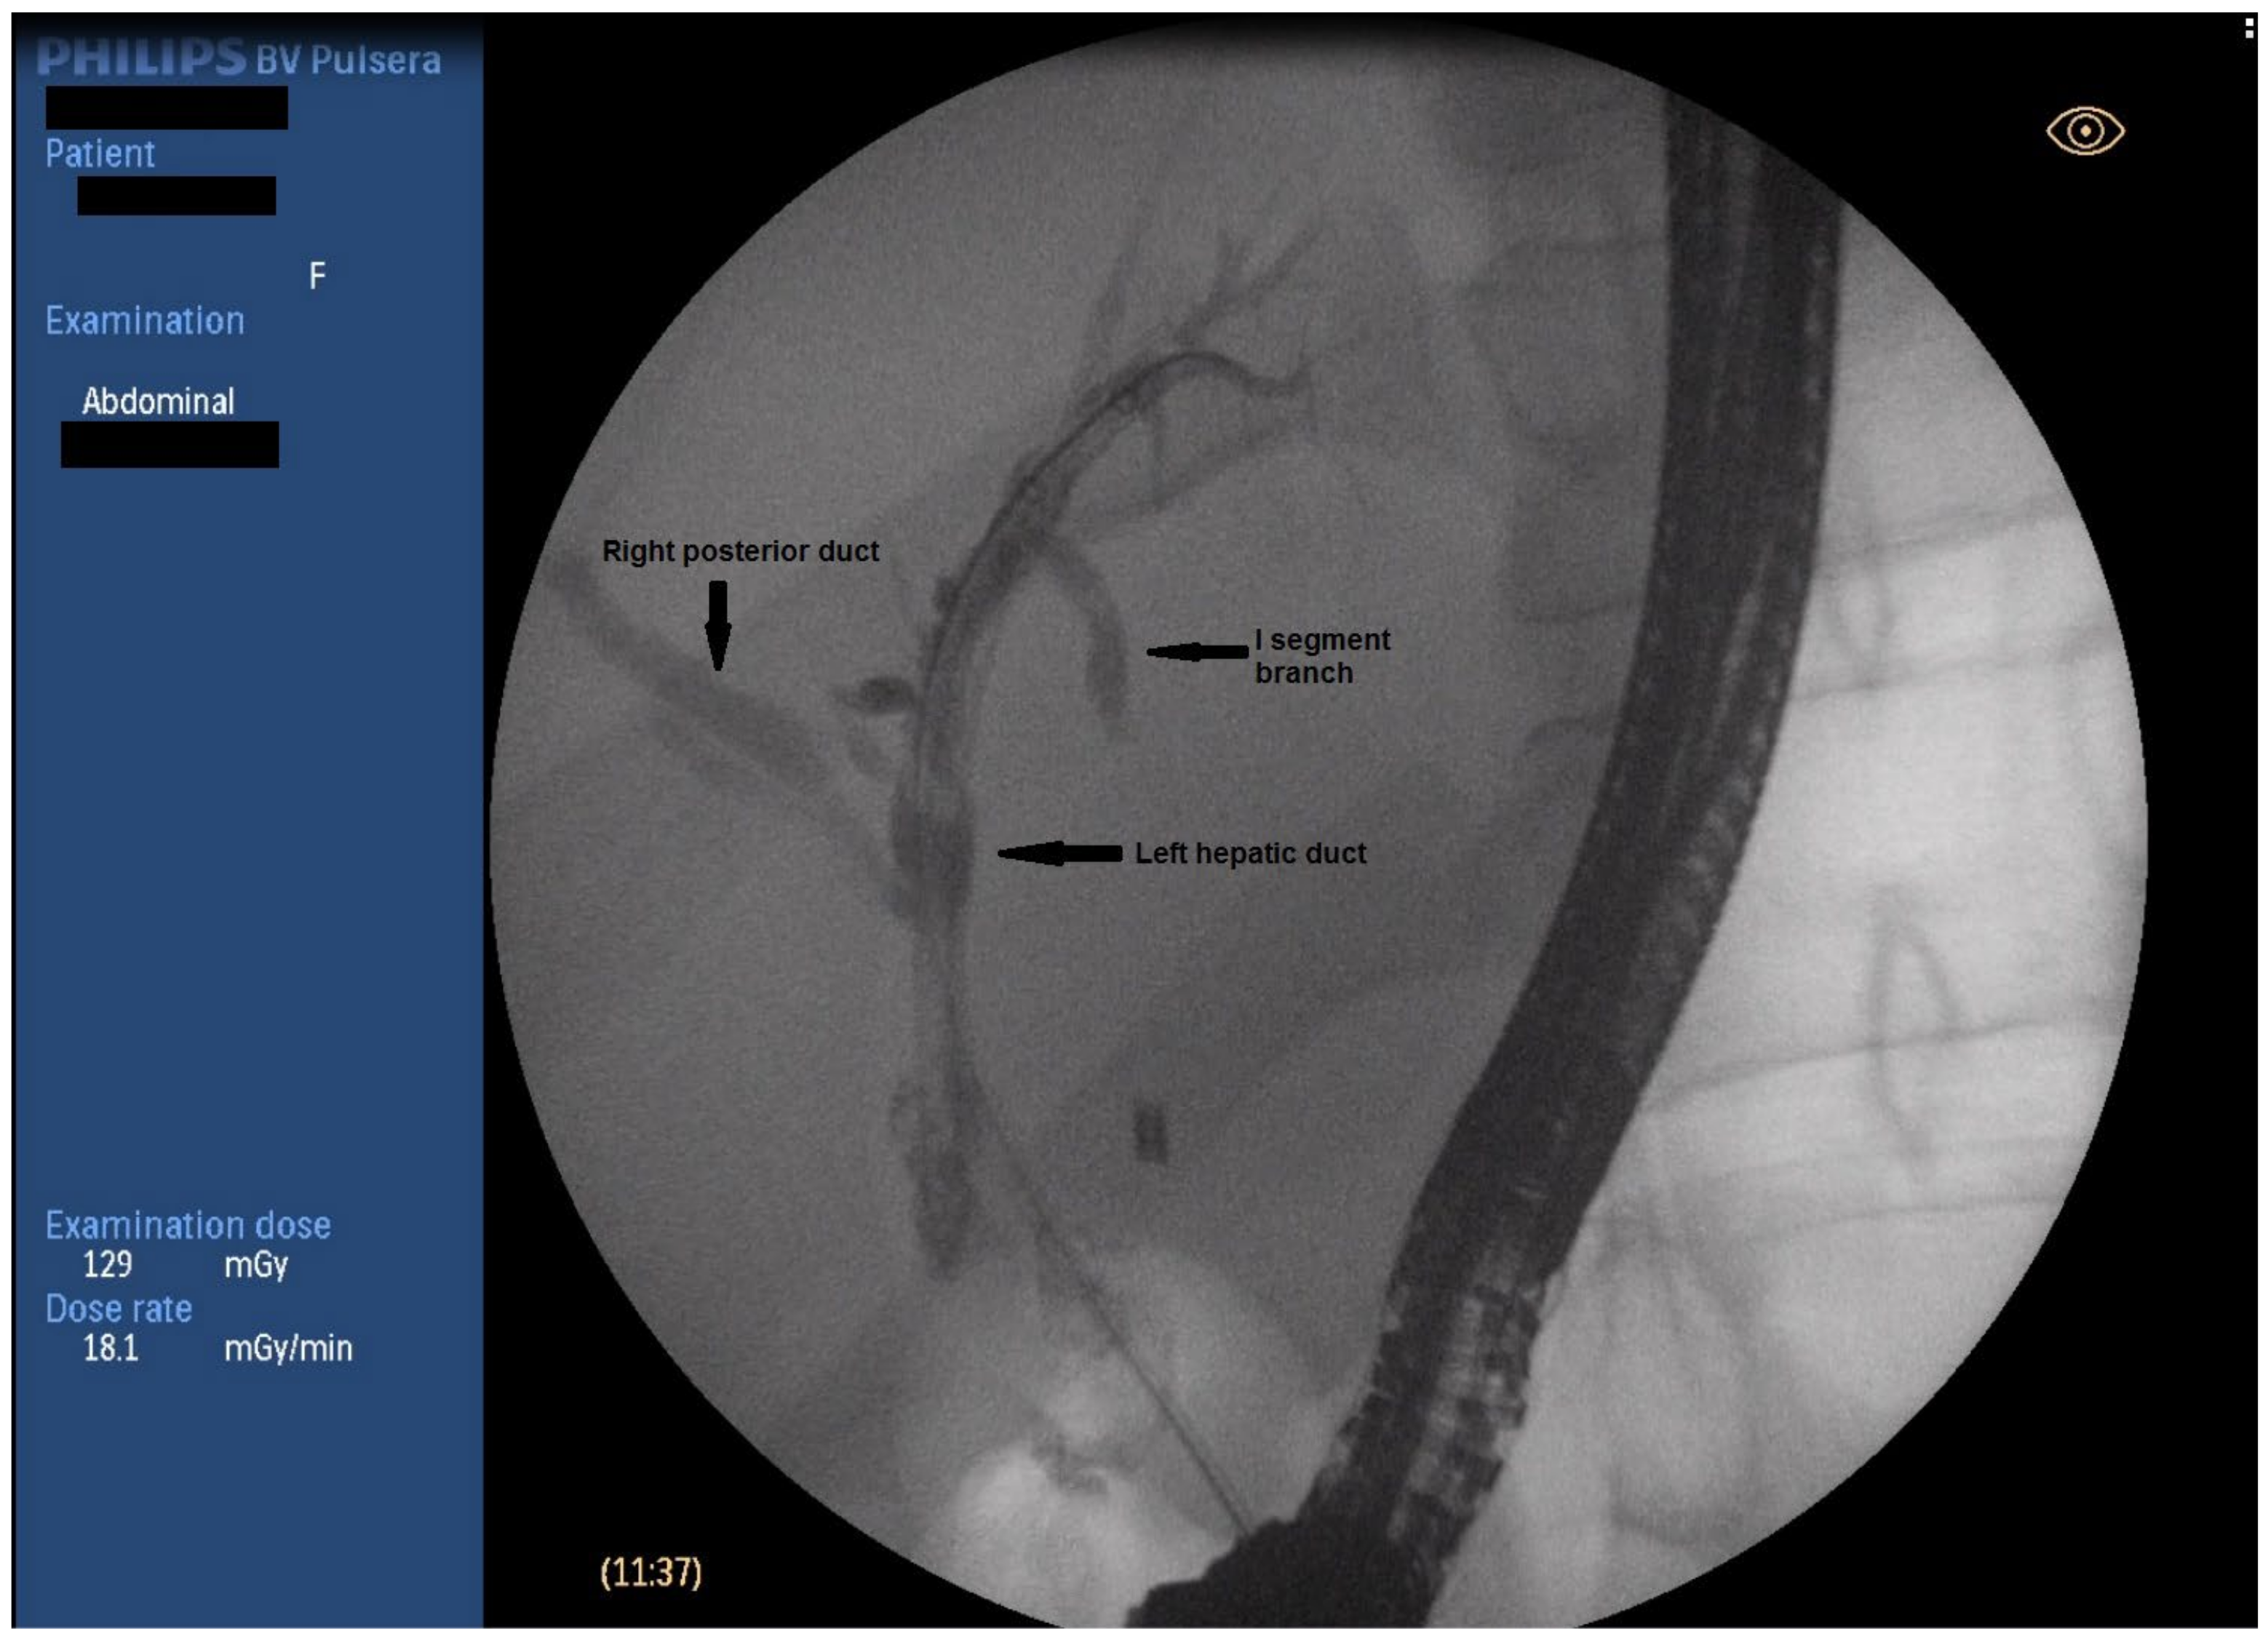

ERCP was performed in line with the described protocol. Upon transpapillary cannulation, no dynamic in the fluoroscopic finding was noted—non-dilated CBD, with proximal obstruction caused by a clip at the level of CHD. Careful withdrawal of the duodenoscope, however, revealed a fistulous opening at the level of bulbus duodeni with a flow of bile. Bilio-digestive fistula was naturally suspected. The fistulous opening was cannulated using a sphincterotome and a 0.025-inch straight guidewire (Figure 1). A short stricture was noted about 10 mm proximal to the fistulous opening, which was initially hard to negotiate through, but eventually, deep biliary cannulation was achieved. Fluoroscopy showed then a biliodigestive fistula formed between duodenum and the left hepatic duct (LHD), with a high-grade stenosis at the distal end of the duct. Further opacification of the biliary tree revealed an anatomical variation of the bile ducts with the right posterior duct draining into the left hepatic duct (Type 3A according to the intrahepatic duct anatomy classification; see Appendix A) (Figure 2). Considering this fact as well as the lack of clinical signs of cholangitis, it was decided that stenting of the left hepatic duct would ensure adequate biliary drainage and might preclude the need for surgery. The stricture was dilated to 8 mm using a biliary balloon dilation catheter (Hurricane Rx, Boston Scientific, Marlborough, MA, USA) and two straight plastic stents were inserted (Endoflex, Hamburg, Germany)—7 fr/6 cm in the 2nd segment branch and 10 fr/6 cm 3rd segment branch (Figure 3). There were no adverse events (AE) defined according to the European Society for Gastrointestinal Endoscopy (ESGE) and American Society for Gastrointestinal Endoscopy (ASGE) guidelines [9,10]. The patient was discharged 3 days later, with readmission for reevaluation planned six months later.

Figure 2.

Fluoroscopic image of biliary anatomy.

To our knowledge, this is the first case to report endoscopic management of spontaneous hepatico-duodenal fistula, following iatrogenic BDI. Several facts were taken under consideration. Firstly, since the diagnosis was set in the course of ERCP and up on successful cannulation of the intrahepatic bile ducts, it was decided that management of the stricture as any other benign biliary stricture is a viable option. Additionally, though high-grade, the stenotic region was quite short, which was considered favorable. Upon cholangiography, the fistulous tract was established to be between the left hepatic duct and duodenum. This would preclude endoscopic treatment, but as already mentioned, further fluoroscopic evaluation found a variation of biliary anatomy with the right posterior duct draining into the left hepatic duct (Type 3A according to the intrahepatic duct anatomy classification; see Appendix A). The lack of cholangitis and the opportunity to drain at least six liver segments avoiding major surgical procedure drove our decision to attempt endoscopic therapy. The patient’s preferences were also accounted for.